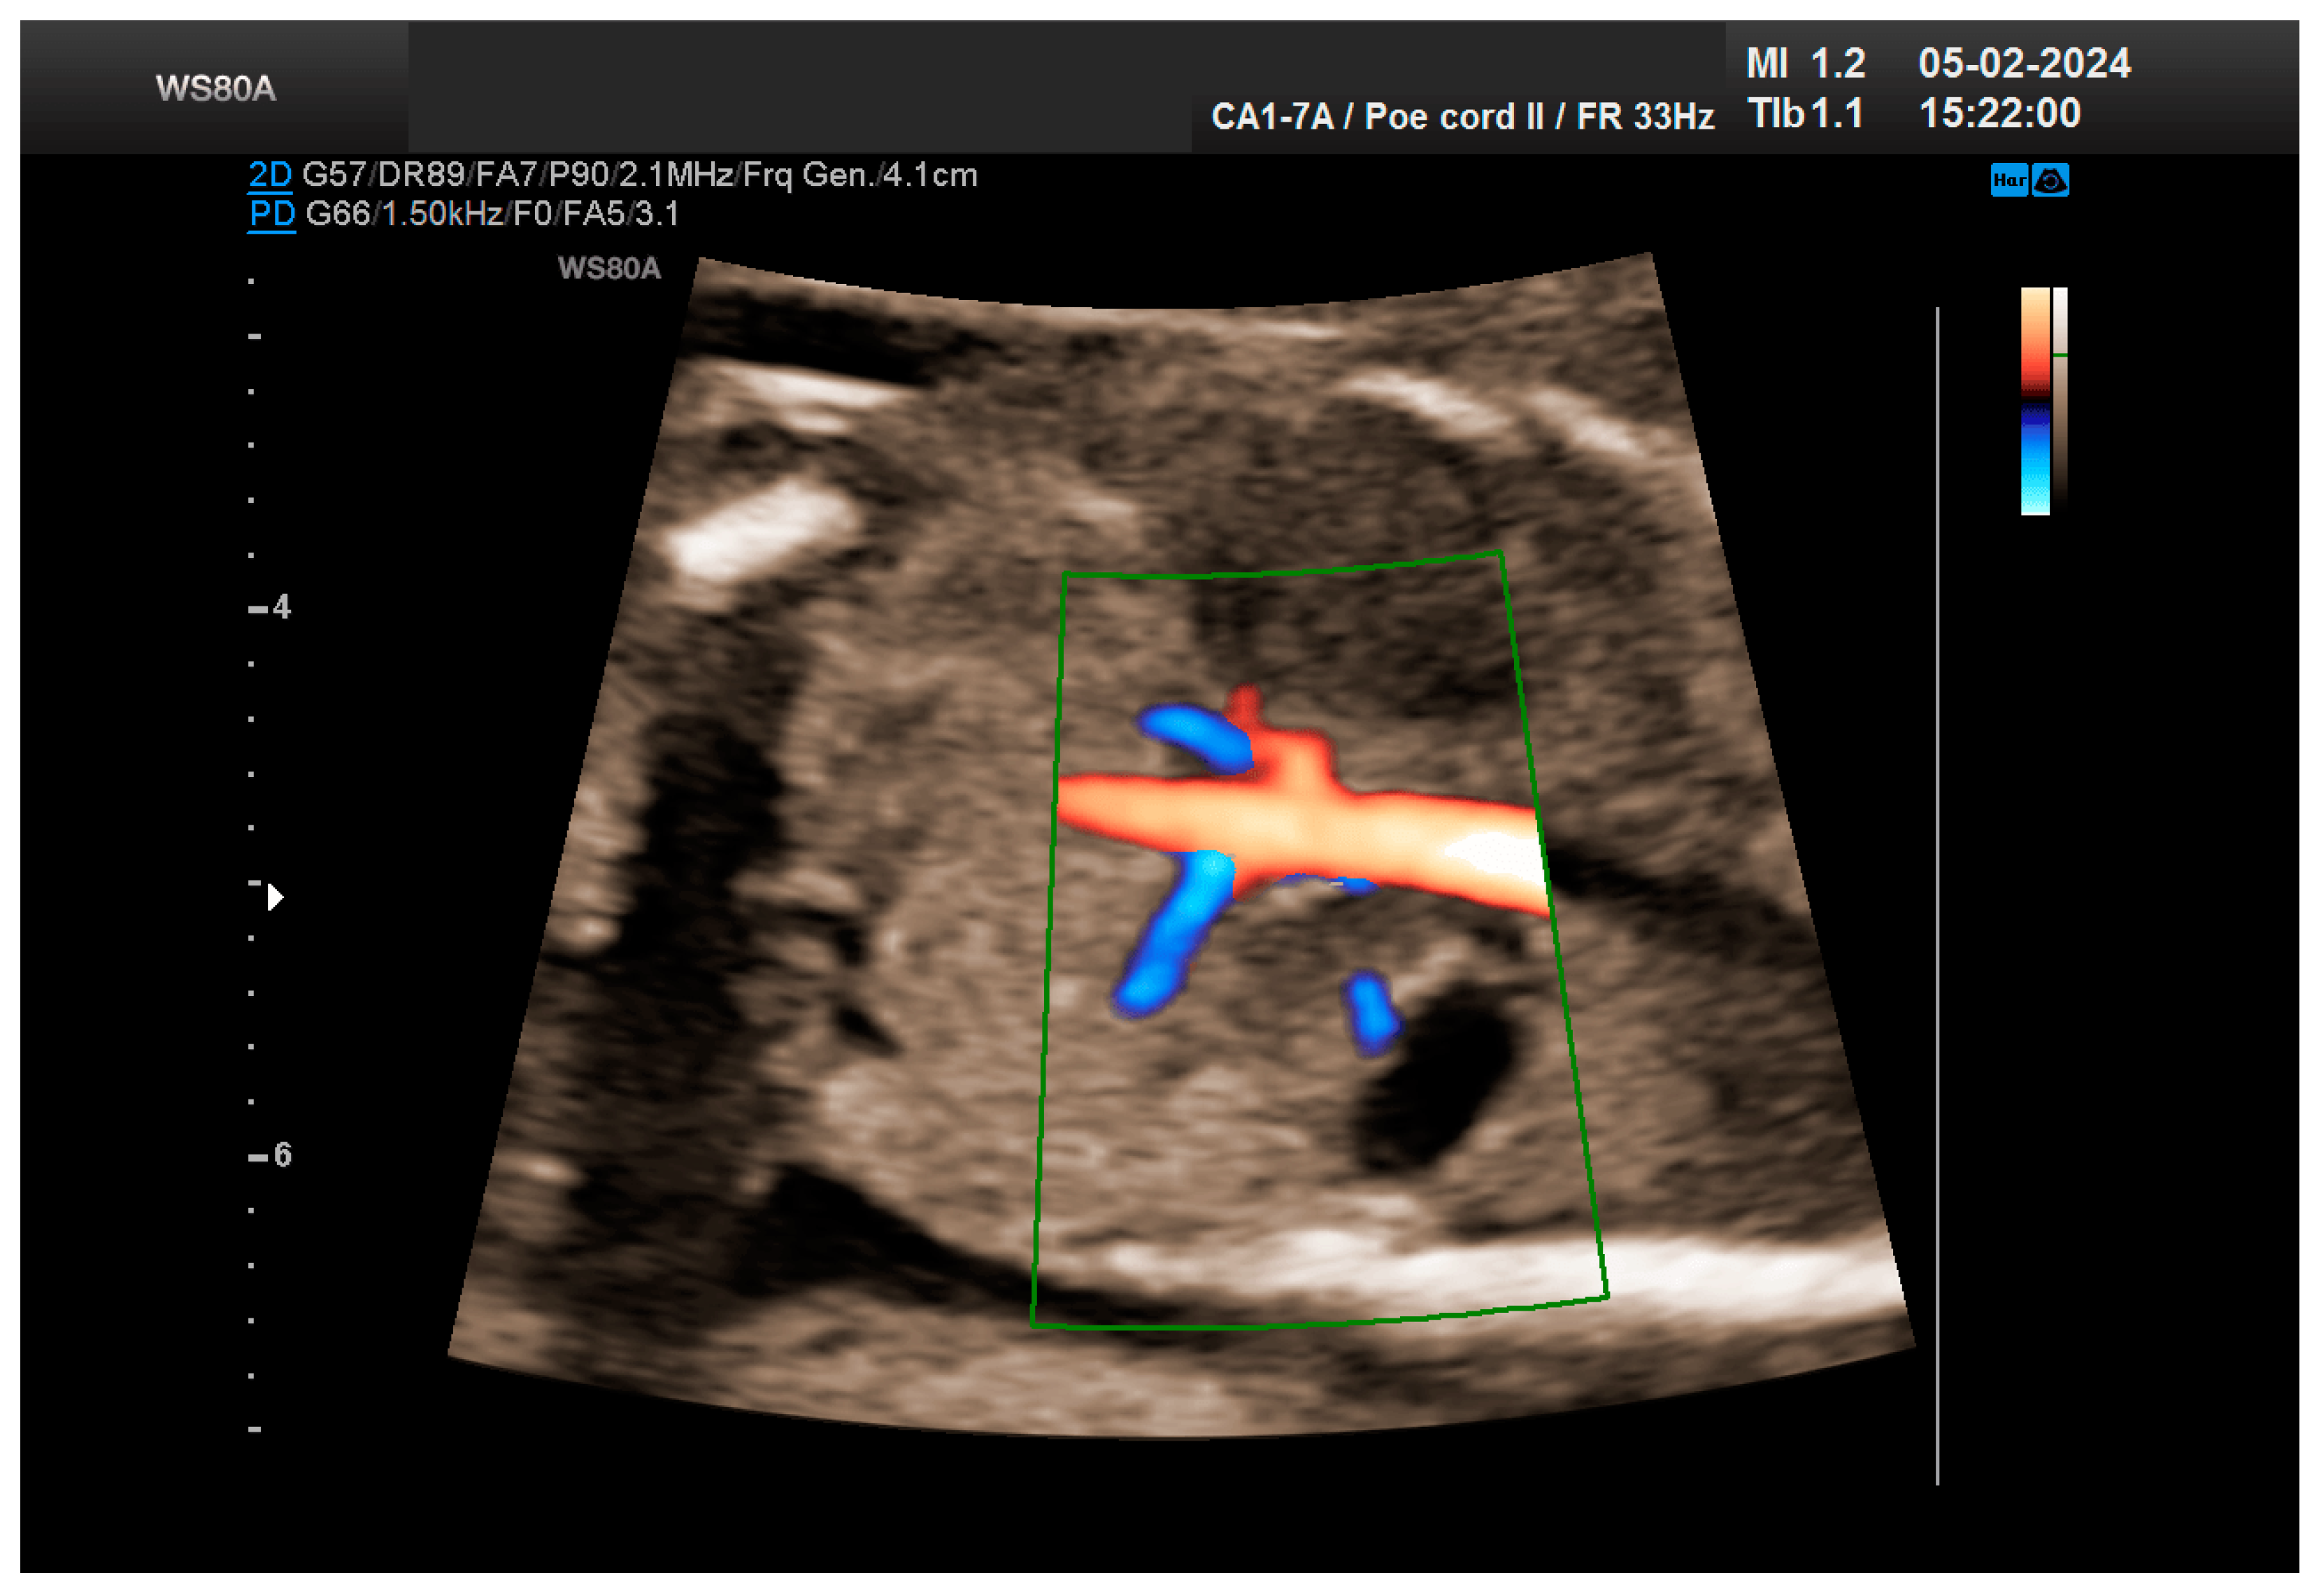

The patient returned at a gestational age of 22 weeks for a second-trimester ultrasound screening. During this examination, the suspicion of crossed fused renal ectopia was confirmed. Axial sections revealed a normal kidney image in the left lumbar fossa and another one, anterior to the spine, without reaching the right renal fossa, fused with the normal left kidney (Figure 5). Two sources of arterial vascularization could be identified, both of them with origins in aorta as follows: one correctly originating from the lumbar aorta, serving the normally positioned left kidney, and another appearing to originate on the anterior border of aorta, at the same level, supplying the ectopic right renal tissue mass (Figure 4 and Figure 6). The bladder was present, with normal appearance and volume. No left ureterohydronephrosis was detected. The presence and course of the right ureter could not be identified. The amniotic fluid volume was normal. No other severe or minor anomalies were observed.

Figure 6. The two kidneys fused with aortic arterial vascularization. Green box—color Doppler window.